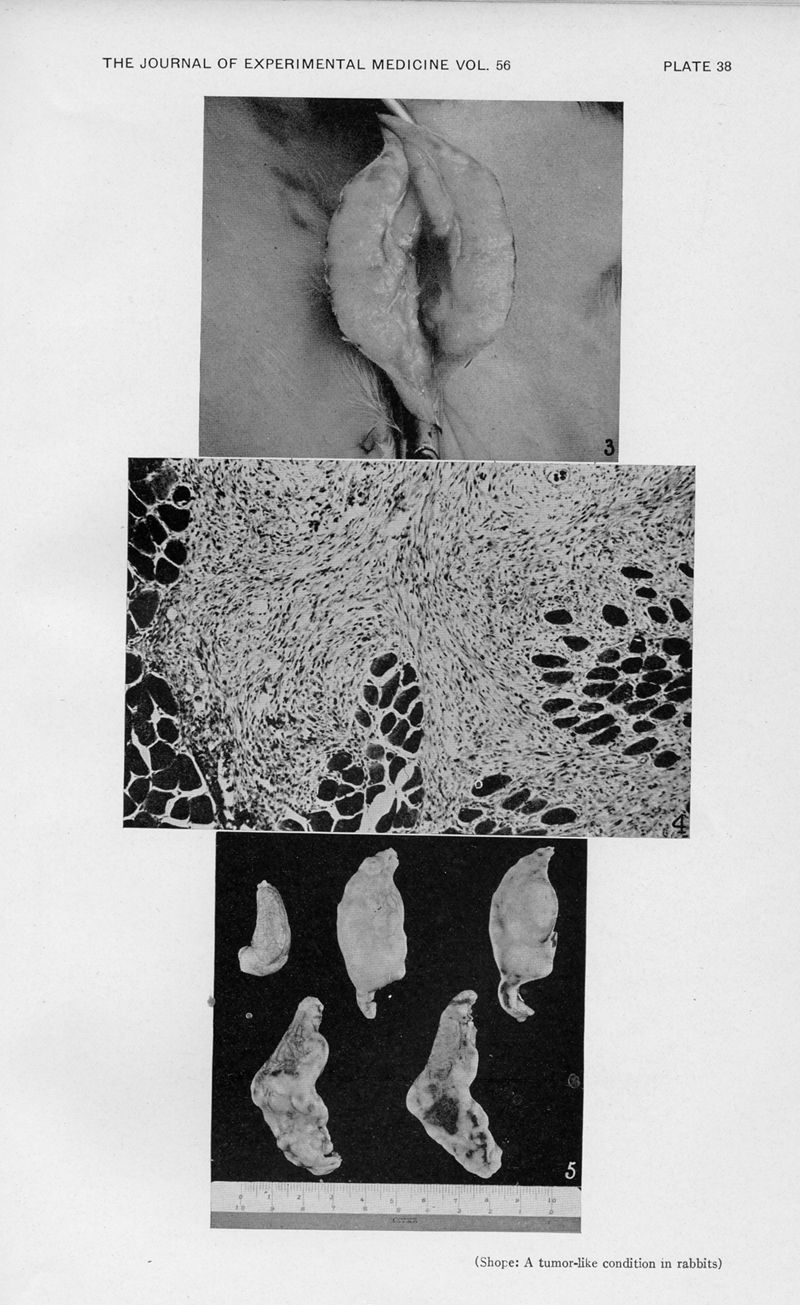

SHOPE, Richard Edwin.

In : Journal of experimental medicine,

1932, Vol. 56, pp. 793-802

SHOPE, Richard Edwin.

In : Journal of experimental medicine,

1932, Vol. 56, pp. 793-802